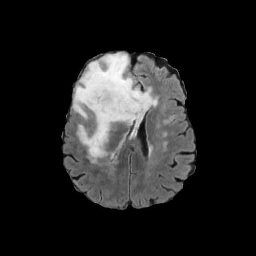

Refer to caption

(a) CT images.

(b) MRI images.

Figure 6: Lossy compression based attack on CT images (a) and MRI images (b) with a specific channel numbers (C8050\mathrm{C^{50}_{80}}) for the EP and IT Scenarios. StolenEPD1\mathrm{Stolen}^{\mathrm{D1}}_{\mathrm{EP}} denotes the decompressed images in the EP Scenario with a reduced D1 decoder.

Compression-Fidelity Compromise. Based on the previous results, we have selected the decoder D1D1 and the configuration of the latent and hyperlatent variables C8050\mathrm{C^{50}_{80}}, as the optimal architecture of the HiFiC encoder-decoder pair. In Fig. 6, we display more specifically the compression and reconstruction quality performances. In terms of reconstruction quality, we obtain a PSNR of approximately 40 for CT images and around 38 for MRI images while the MS_SSIM values are close to 1. This indicates an excellent perceptual quality of the reconstructed images that are hardly discernible from the original ones. In terms of compression efficiency, the Pratio\mathrm{P}_{\mathrm{ratio}} for CT images is approximately 0.015, indicating that the lossy image compression-based attack generated compressed images are 67 times smaller than those produced by the lossless zipped image compression-based attack. For MRI images, the Pratio\mathrm{P}_{\mathrm{ratio}} is around 0.12, 10 times higher than that of CT images, which can be attributed to the presence of a large uniform background in the skull-stripped original MR images.